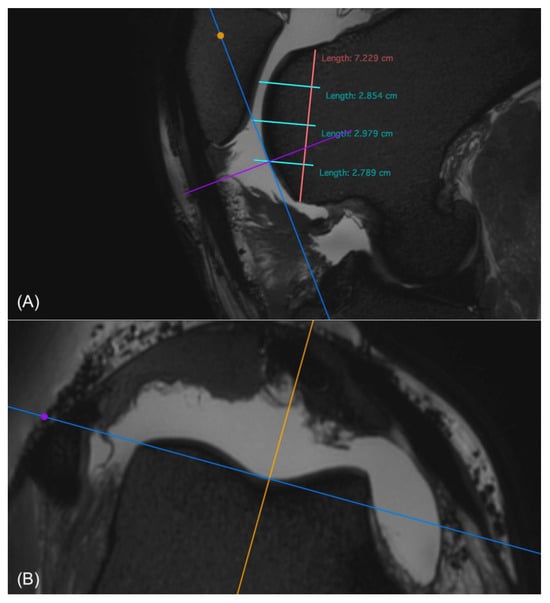

Figure 3. (A) Sagittal and (B) transverse view of the trochlear groove in a 3D T2-weighted image where the regions of interest (ROIs) were determined. The ROIs are marked as described in Figure 1 and Figure 2 (A). To measure the cartilage thickness in the transverse image (B) at the same ROI, the cross of the transverse (purple) and dorsal (blue) planes was placed at the ROI in the sagittal view (A). This automatically places the plane cross on the same ROI in the transverse view (B). Care was taken to place the transverse plane (purple) perpendicularly to the cartilage surface at the point of measurement. This was carried out for all ROIs in the femoropatellar joint. For the femorotibial joint the dorsal view was used instead of the transverse.